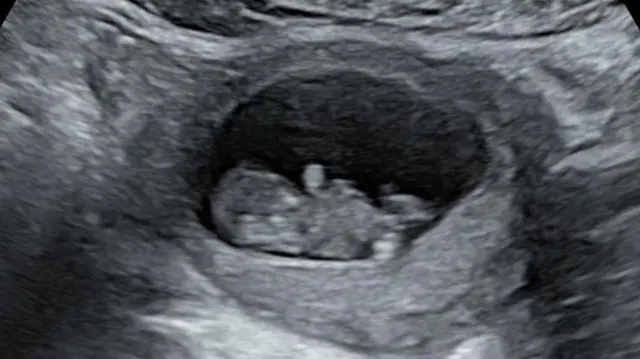

Mas, após um sangramento no início da gravidez, um teste mostrou que Rhiannon havia sofrido um aborto espontâneo com oito semanas.

Em outubro do ano passado, ela descobriu que estava grávida novamente e, desta vez, ficou mais tranquila com alguns exames iniciais.

Mas então veio o ultrassom de 20 semanas, que revelou que o bebê – que o casal chamou de Hudson – tinha uma forma grave de síndrome do coração esquerdo hipoplásico, uma doença cardíaca congênita rara em que o lado esquerdo do coração é subdesenvolvido.

"Não havia como seguir em frente", diz ela, e Hudson nasceu morto em março, com 22 semanas.